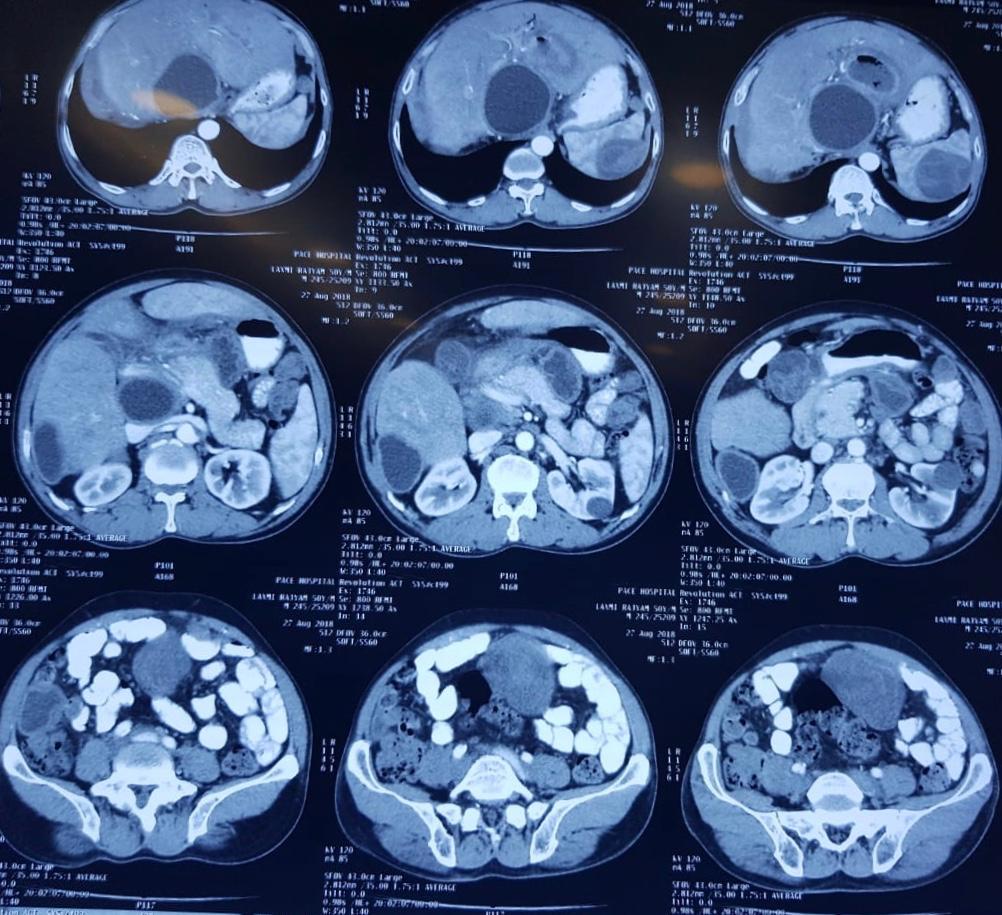

Child’s A CLD with HUGE gastric varices uncontrolled by Endoscopic glue and attempted EUS coiling. One salvage option would be TIPSS with balloon vascular occlusion but due to logistics we went for modified sugiura procedure. Splenectomy + Gastro esophageal devascularisation with anterior Gastrotomy and overseeing of gastric varices with pyloroplasty. Images show 1 CECT showing large gastric fundal varices. 2,3,4 Gastro Esophageal devasc 5, 6 Large fundal varices before and after oversewing. 7. Anterior gastrotomy 8. Pyloroplasty. Postoperative recovery was uneventful.